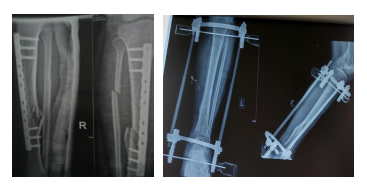

(二)手術治療

1.螺絲釘內(nèi)固定:用于斜行或螺旋形骨折,可采用螺絲釘內(nèi)固定。

2.鋼板內(nèi)固定:斜行、橫行或粉碎性骨折均可應用。

3.髓內(nèi)針內(nèi)固定:多段骨折為防止成角畸形可用髓內(nèi)釘固定。

4.外固定架:皮膚嚴重損傷者可采用外固定架固定骨折斷端。